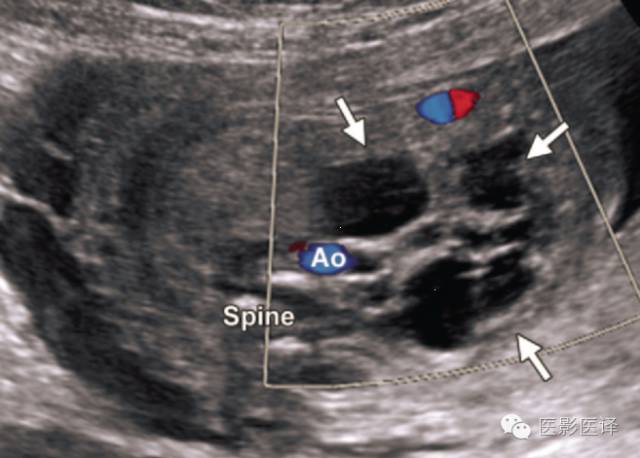

图9.MCDK.胎儿的彩色多普勒超声横断位图像显示一个多囊性占位(箭),邻近脊柱和主动脉(Ao)。这是MCDK的典型影像表现。